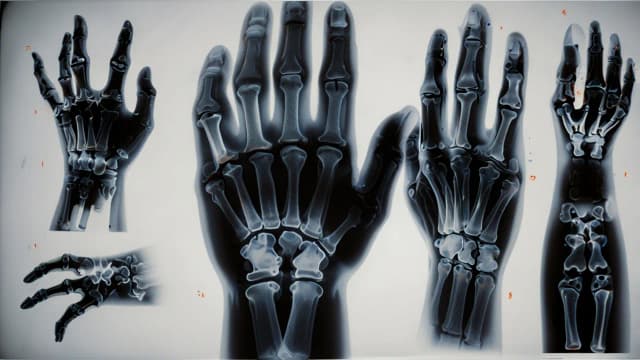

Złamany palec: objawy, które musisz znać - poradnik pacjenta

Poznaj kluczowe objawy złamanego palca u ręki lub nogi. Dowiedz się, jak odróżnić złamanie od stłuczenia i kiedy konieczna jest wizyta u lekarza. Szybka diagnoza to klucz do skutecznego leczenia!